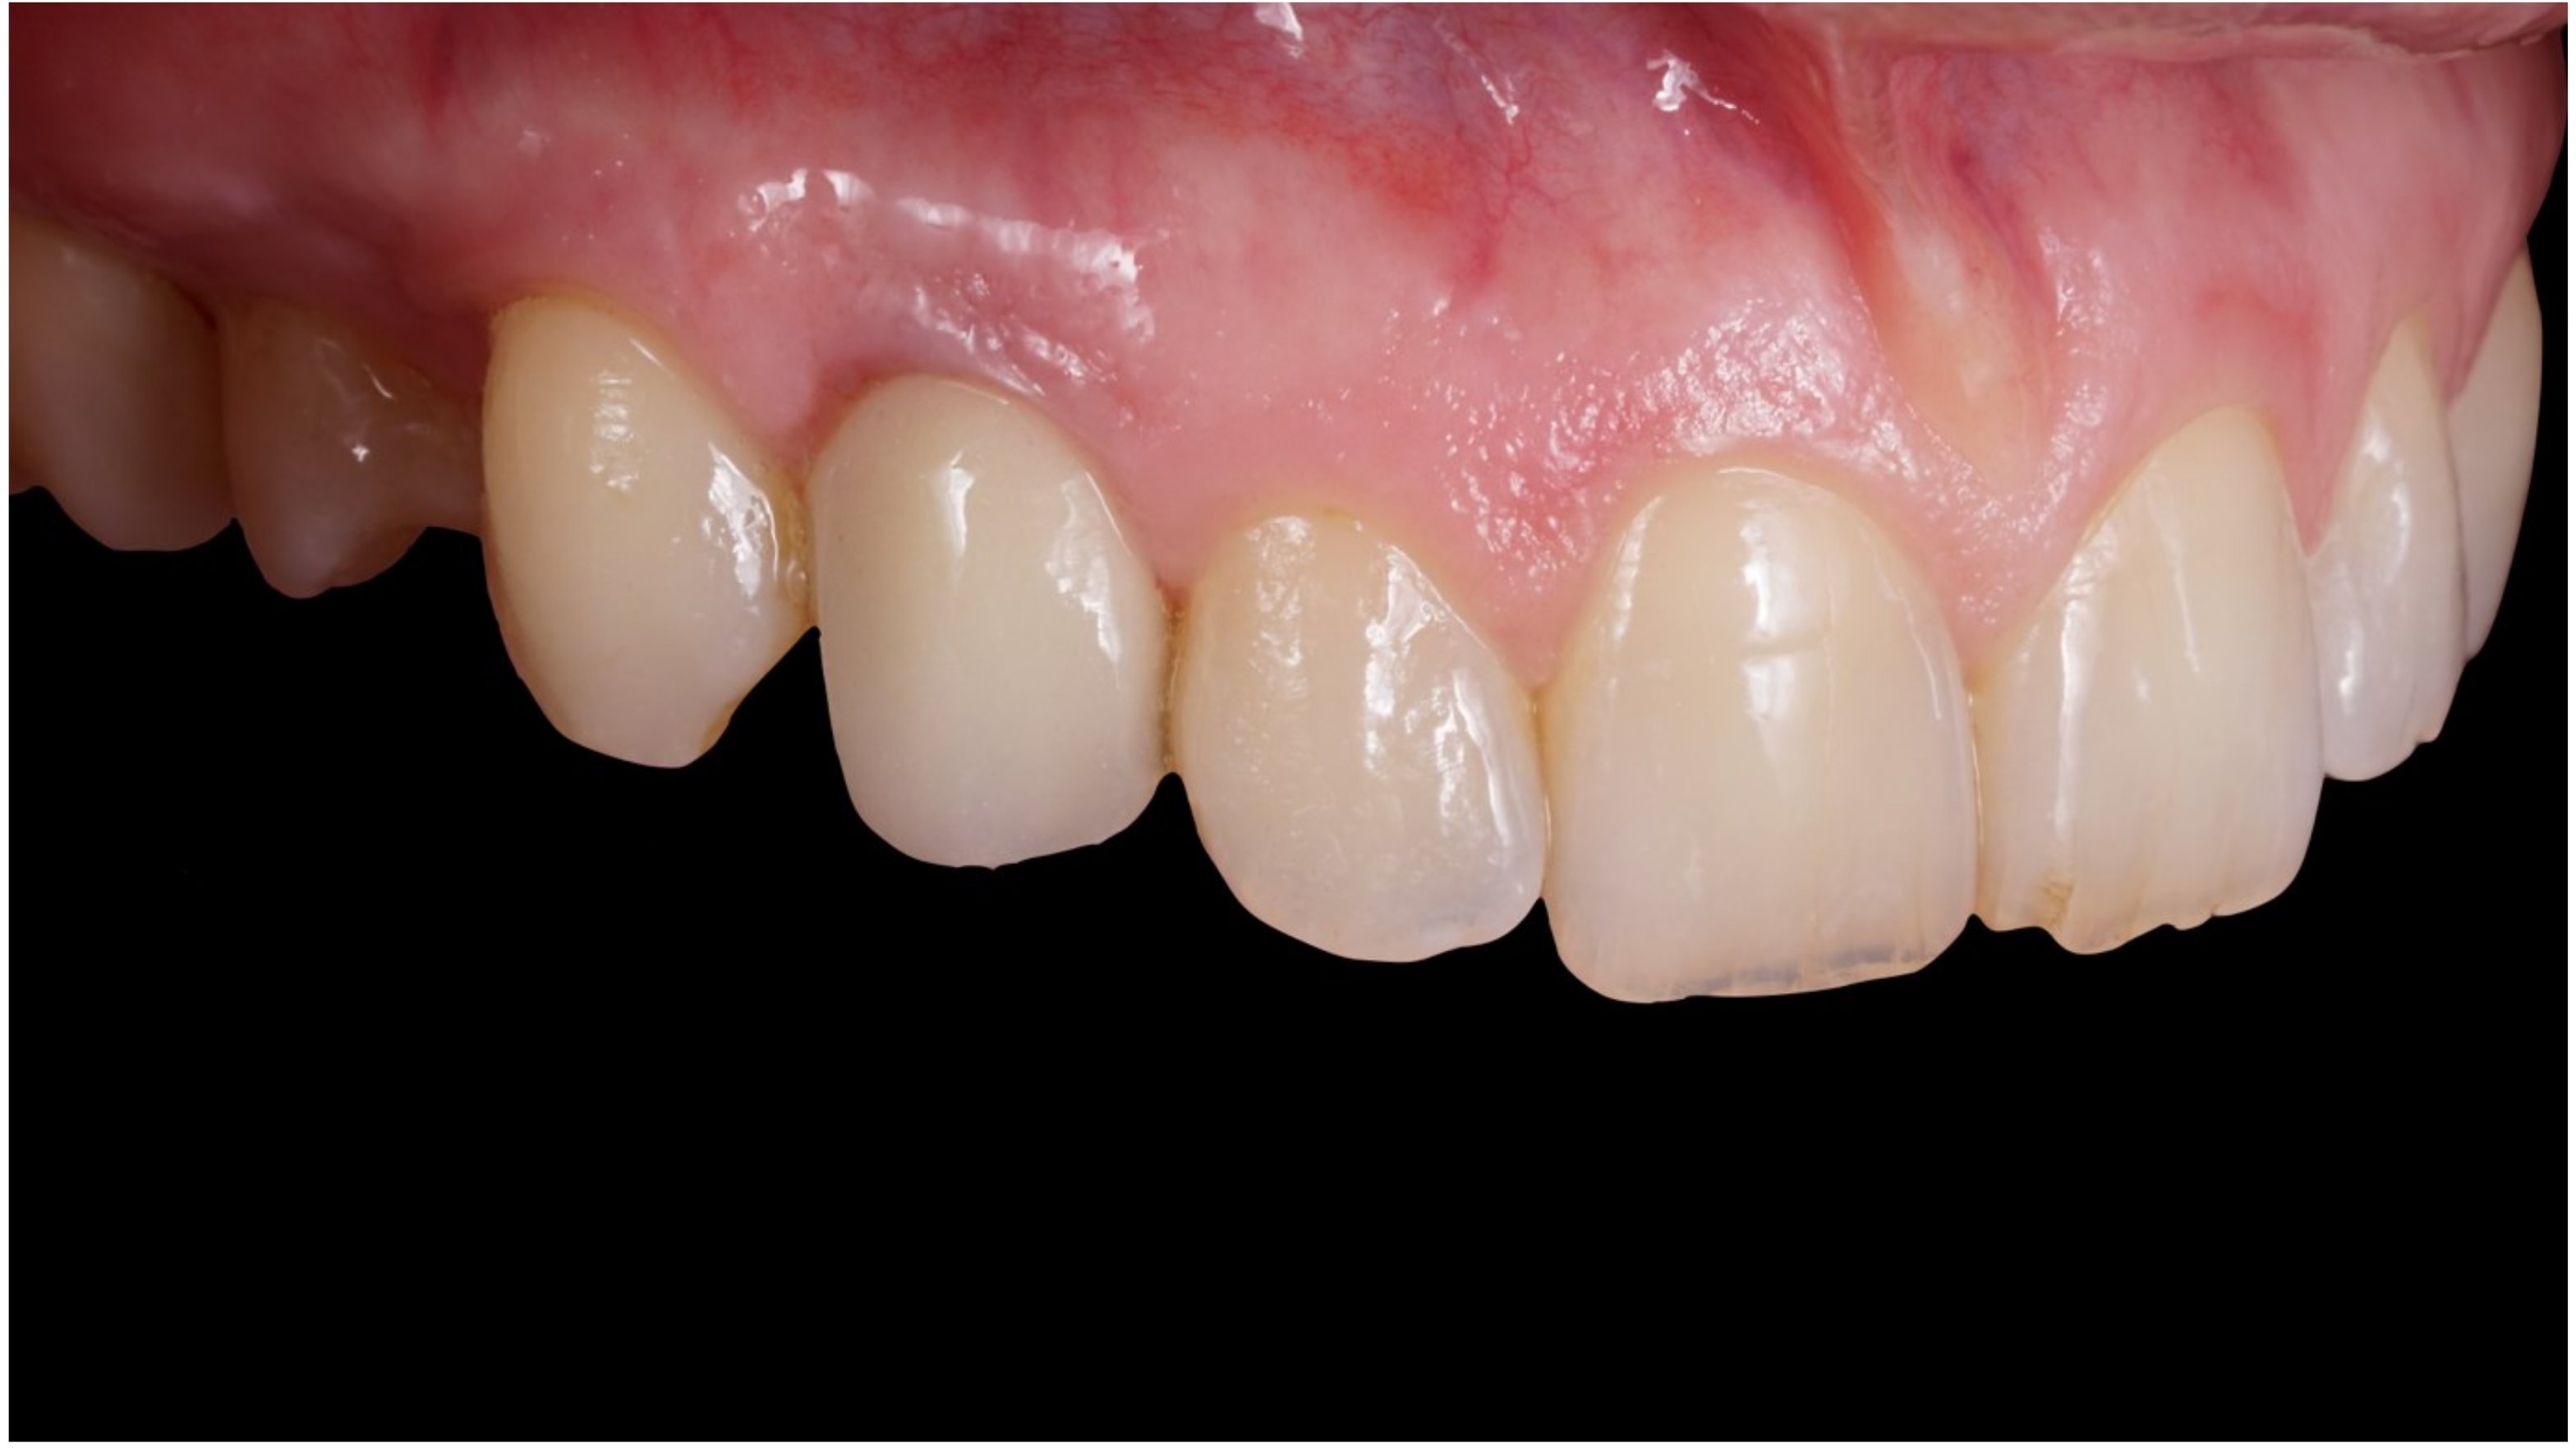

Figure 1.

Preoperative frontal view.

Figure 2.

Lateral preoperative view.